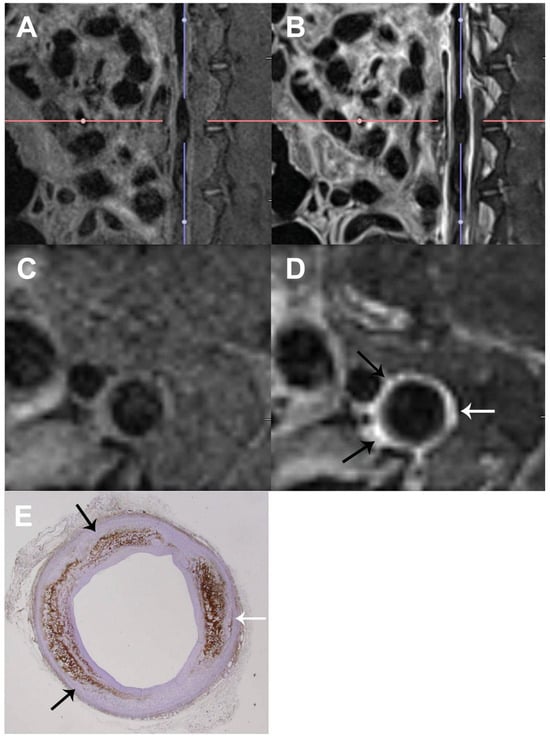

- Becher, T.; Riascos-Bernal, D.F.; Kramer, D.J.; Almonte, V.M.; Chi, J.; Tong, T.; Oliveira-Paula, G.H.; Koleilat, I.; Chen, W.; Cohen, P.; et al. Three-Dimensional Imaging Provides Detailed Atherosclerotic Plaque Morphology and Reveals Angiogenesis After Carotid Artery Ligation. Circ. Res. 2020, 126, 619–632. [Google Scholar] [CrossRef] [PubMed]

- Becher, T.; Riascos-Bernal, D.F.; Chi, J.; Cohen, P.; Sibinga, N. Three-Dimensional Visualization of Atherosclerotic Vessels by Tissue Clearing and Light-Sheet Fluorescence Microscopy. Methods Mol. Biol. 2022, 2419, 841–851. [Google Scholar] [CrossRef] [PubMed]

- Cartaya, A.E.; Maiocchi, S.; Buglak, N.E.; Torzone, S.; Messinger, G.; Bahnson, E.S.M. Application of Machine Learning and Virtual Reality for Volumetric Analysis of Arterial Lesions. BioRxiv 2023. [Google Scholar] [CrossRef]